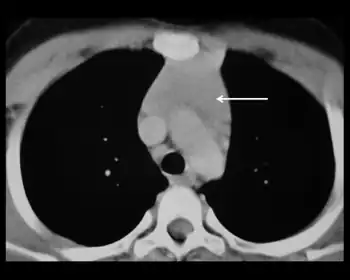

Thymus hyperplasia refers to an enlargement ("hyperplasia") of the thymus.[1]

It can be associated with myasthenia gravis.[2][3] Magnetic Resonance Imaging can be used to distinguish it from thymoma.[4]